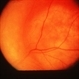

- Choroidal Osteoma

- Orange, pale yellow, plate-like choroidal lesion with a bone density.